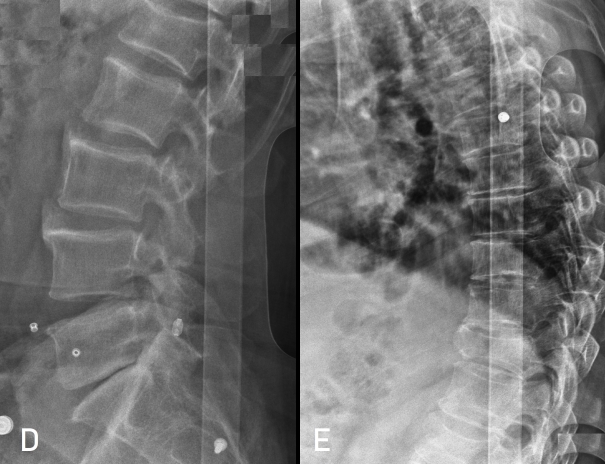

Postoperatif Direkt Grafi - Kifoplasti ve Stabilizasyon

Resim 4: Ameliyat sonrası (postop) direkt grafilerde T9 ve L1 kifoplasti, T10-11-12 transpediküler stabilizasyon görülmektedir.

Hastaya T9 ve L1 vertebralarına kifoplasti (6'şar ml metilmetakrilat) ve T10-11-12 vertebralarına transpediküler stabilizasyon uygulandı. Laminalar ve fasetler üzeri kısmi dekortike edilerek füzyon artırıcı (Ca-fosfat granül) materyal ve alandan alınan otojen kemikler serildi. T11 laminası ve faset ekleminin iki yanlı kırık olduğu görüldü. Laminektomi yapılmadı.